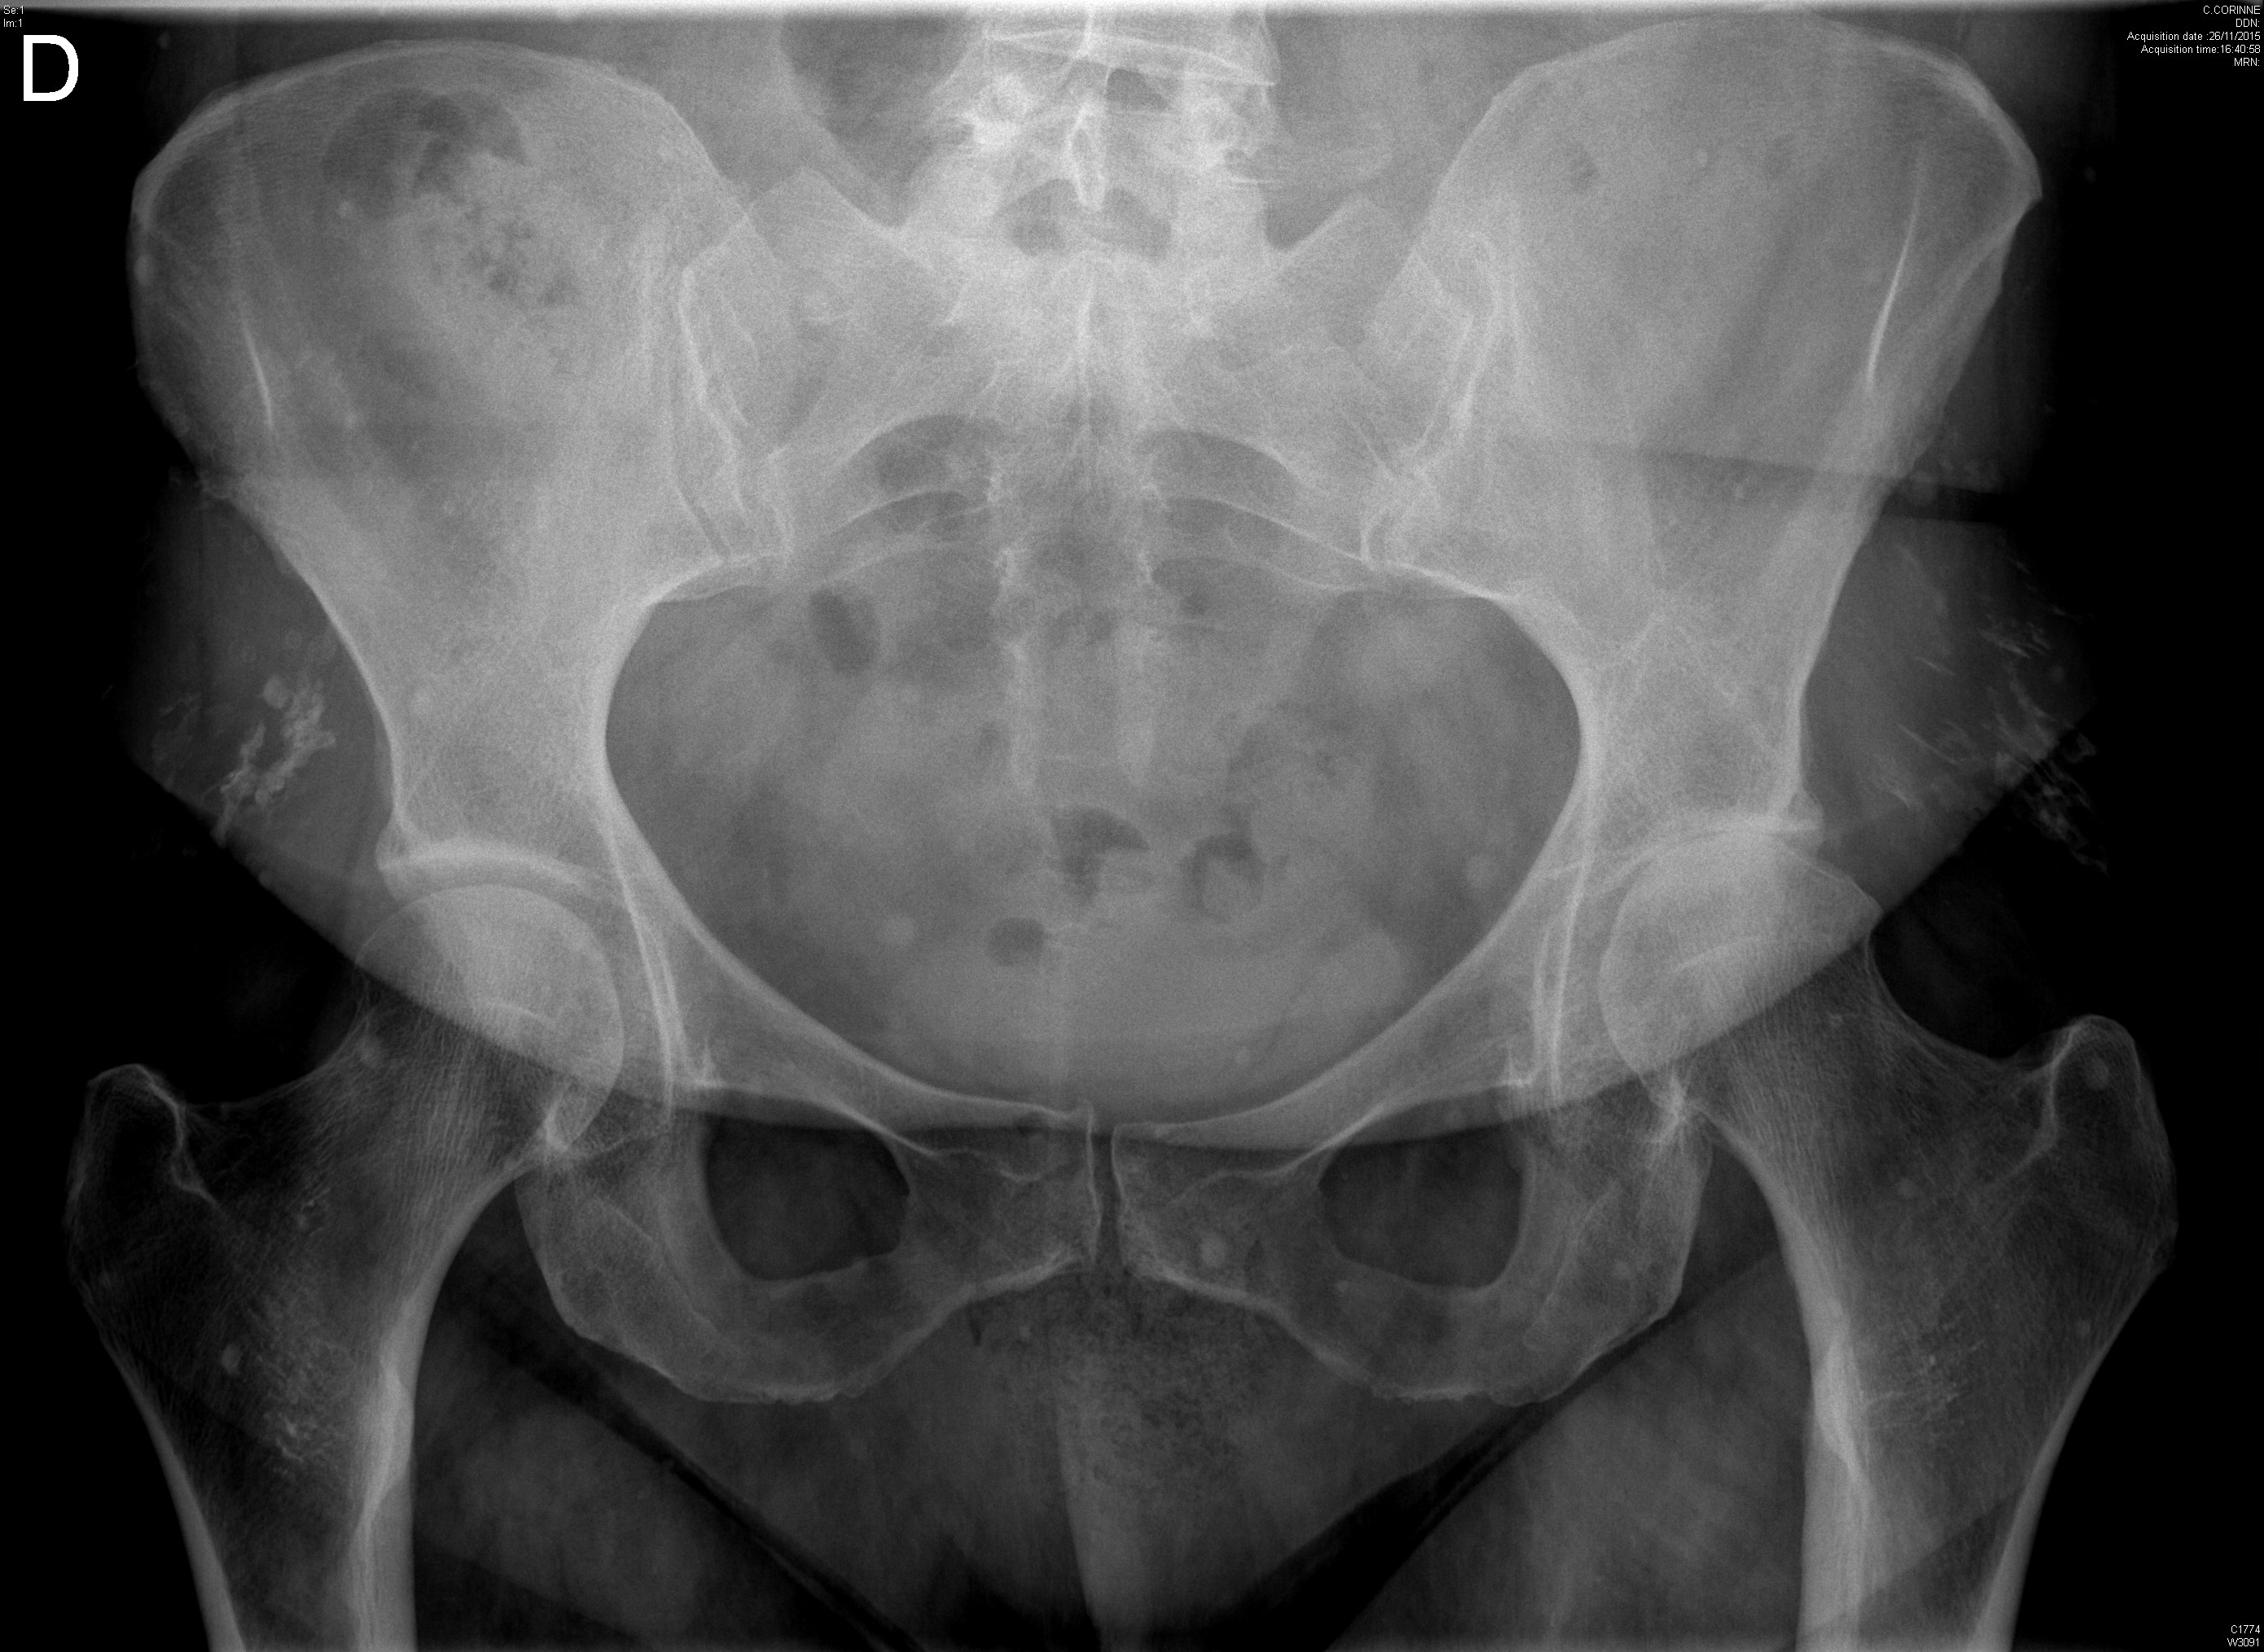

Radiographie retrouvant une dysplasie acétabulaire bilatérale ainsi qu'une lésion de dysplasie fibreuse du col fémoral droit chez une jeune fille